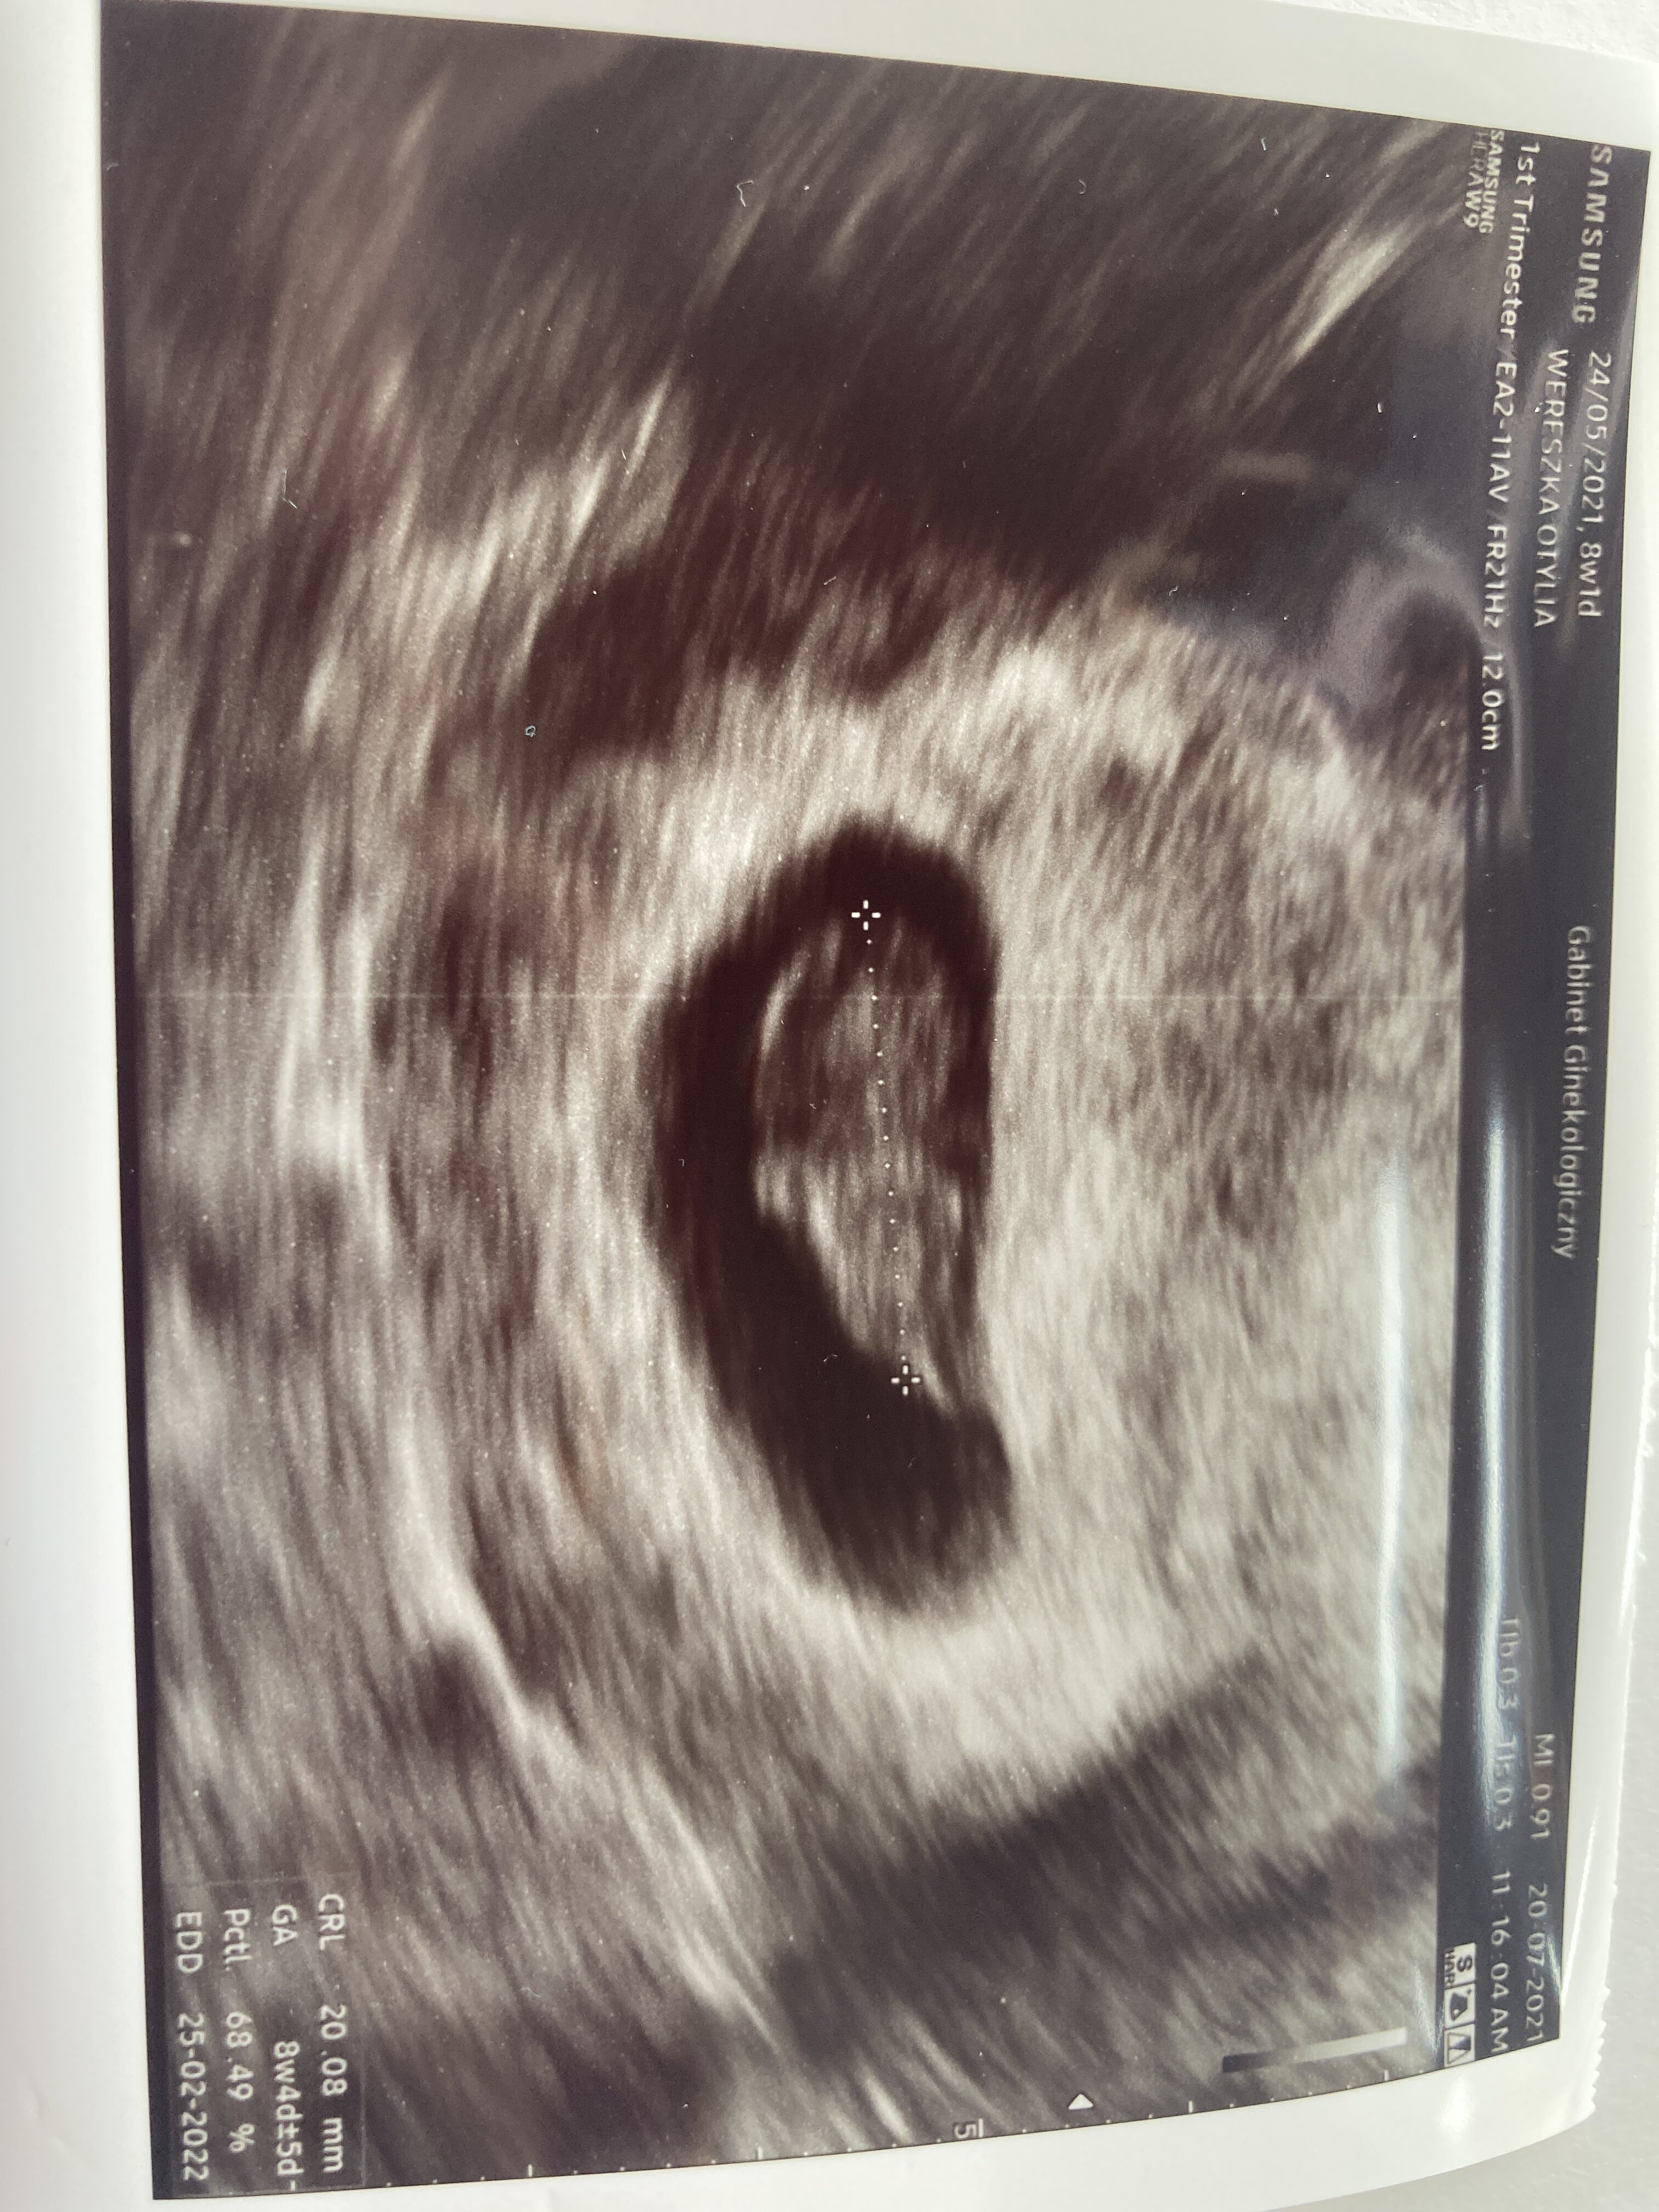

Jest wszystko ok kolejna wizyta za miesiąc a prenatalne wcześniej. Poród usg teraz wyszedł teraz 25.02.2022 😱 2 cm szczęścia serce bije 164.

Załączniki

• 5D072A96-83BC-4200-9E33-7A4B177B9E46.jpeg

5D072A96-83BC-4200-9E33-7A4B177B9E46.jpeg

1,8 MB · Wyświetleń: 111